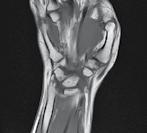

Reducerea artroscopică și fixarea internă a unei fracturi articulare cominutive de epifiză distală de radius cu fragment „die-punch”- prezentare de caz Dr. Daniel Vîlcioiu, Claudiu Jaba